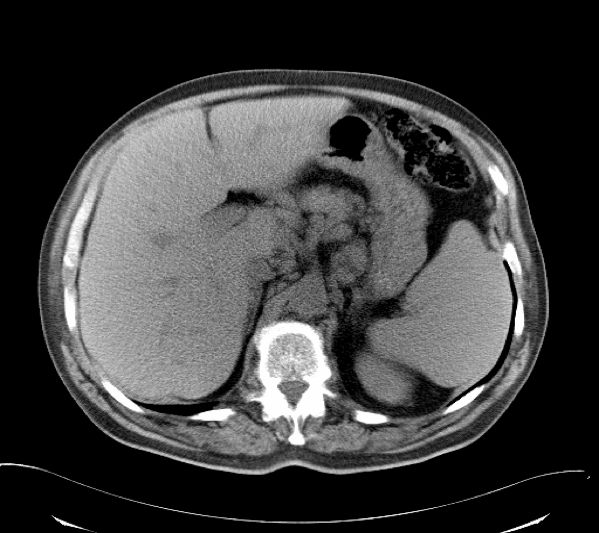

高原子序数或吸收系数大的物体部分投影于扫描平面而产生的伪影称为部分容积效应,也可称为Hounsfield伪影。一般在重建后横向面图像上可见条形,环形或大片干扰的伪影。 部分容积效应可用正确摆放病人的体位,或采用薄层扫描而减弱。

(部分容积效应)